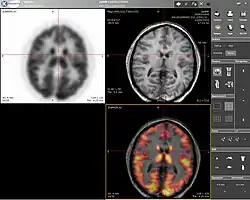

Imágenes neurológicas

IRM es la herramienta escogida para cánceres neurológicos frente a tomografía computarizada, al ofrecer mejor visualización de las áreas situadas en la parte posterior de la fosa craneal, conteniendo el tronco encefálico y el cerebelo. El contraste propiciado por la sustancia gris y la sustancia blanca hace las imágenes de IRM sean la mejor opción para muchas condiciones del sistema nervioso central, incluyendo enfermedades desmielinizantes, demencia, enfermedades cerebrovasculares, enfermedades infecciosas, enfermedad de Alzheimer y epilepsia.[23][24] Al ser una técnica que realiza imágenes separadas tan solo por unos pocos milisegundos puede apreciarse cómo reacciona ciertas zonas del cerebro a diferentes estímulos, permitiendo a los investigadores el estudio estructural como funcional de las anormalidades de los trastornos psicológicos.[25] También es utilizado para cirugías estereotácticas guiadas y radiocirugía para el tratamiento de tumores intracraneales, malformaciones arteriovenosas, y otras casos de condiciones que pueden ser tratadas quirúrgicamente usando una herramienta conocida como N-localizer.[26][27][28]